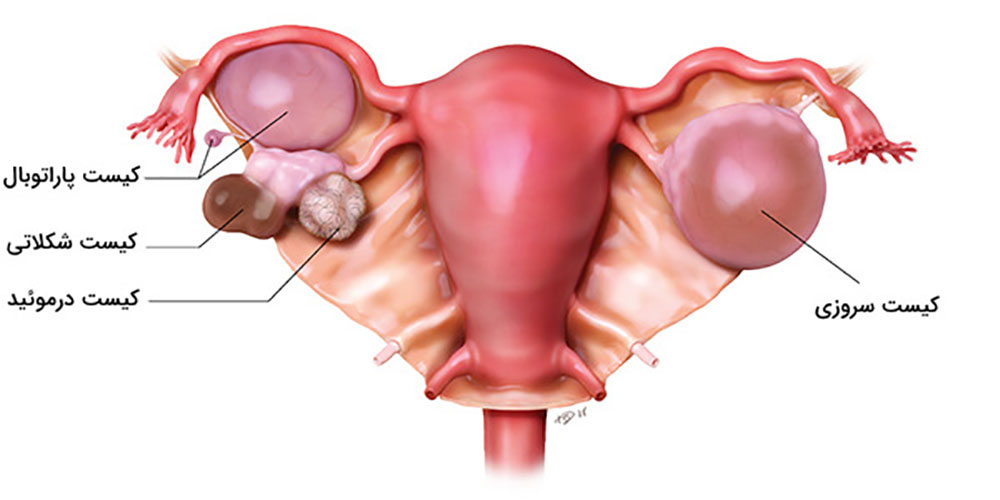

به ندرت، لکه های اندومتریوز در سایر نقاط بدن رخ می دهد. این می تواند باعث ایجاد دردهای غیرعادی در قسمت هایی از بدن شود که همزمان با دردهای پریود رخ می دهد.اندومتریوز باعث می شوددر طول سالیان متمادی تئوری های مختلفی برای علت آندومتریوز وجود داشته است. پوشش داخلی رحم (رحم) آندومتر نامیده می شود. یک نظریه این بود که برخی از سلول های آندومتر به خارج از رحم وارد ناحیه لگن می شوند. وقتی پریود میشوید، با ریختن به سمت عقب در امتداد لولههای فالوپ به آنجا میرسند.لکه های اندومتریوز تمایل دارند "چسبنده" باشند و ممکن است اندام ها را به یکدیگر بپیوندند. اصطلاح پزشکی برای این چسبندگی است. برای مثال، مثانه یا روده ممکن است به رحم «بچسبد». تکه های بزرگ آندومتریوز ممکن است به کیست هایی تبدیل شوند که هر ماه هنگام پریود شدن شما خونریزی می کنند. کیست ها می توانند با خون تیره پر شوند و به عنوان کیست های شکلاتی شناخته می شوند.

تشکیل کیستها: در برخی موارد، اندومتریوز میتواند منجر به تشکیل کیستهایی به نام "اندومتریوما" در تخمدانها شود که ممکن است دردناک باشند و حتی در صورت عدم درمان، به جراحی نیاز پیدا کند.

شناسایی کیستهای اندومتریوز (Endometriomas)

یکی از ویژگیهای بارز اندومتریوز ایجاد کیستهایی به نام اندومتریوما (یا "کیست شکلاتی") است که در تخمدانها یافت میشود. این کیستها از خون و بافت مشابه اندومتر تشکیل شدهاند. سونوگرافی میتواند این کیستها را به وضوح شناسایی کند. در تصاویر سونوگرافی، کیستهای اندومتریوز معمولاً به صورت تودههای گرد و یا بیضی با محتوای داخلی خاص دیده میشوند که ممکن است به رنگ تیرهتر از سایر بافتها ظاهر شوند.

اندومتریوز معمولاً به سطوح صفاقی یا سروزی اندامهای لگنی، معمولاً تخمدانها، رباطهای پهن، کولدساک خلفی و رباطهای رحمی خاجی محدود میشود.

محل های کمتر شایع شامل لوله های فالوپ، سطوح سروزی روده کوچک و بزرگ، حالب، مثانه، واژن، دهانه رحم، اسکارهای جراحی و به ندرت ریه، پلور و پریکارد می باشد.

انواع مختلف اندومتریوز

به گفته متخصصان، آندومتریوز یک نوع نیست، بلکه چندین نوع وجود دارد. در واقع، دو بیمار ممکن است علائم متفاوت یا یکسانی را تجربه کنند، اما از یک زن به زن دیگر با شدت متفاوت. نوع آندومتریوز در درجه اول به محل گسترش بافت آندومتر (آندومتر) بستگی دارد. در 80 درصد موارد، اندومتریوز دستگاه تناسلی را درگیر می کند.

آندومتریوز با وجود بافت آندومتر در خارج از رحم، یعنی روی تخمدانها، لولههای فالوپ، رباطهای ساکرال رحم (رباطهایی که از رحم حمایت میکنند)، صفاق، مثانه، روده و به ندرت ریهها و حتی مغز مشخص میشود.